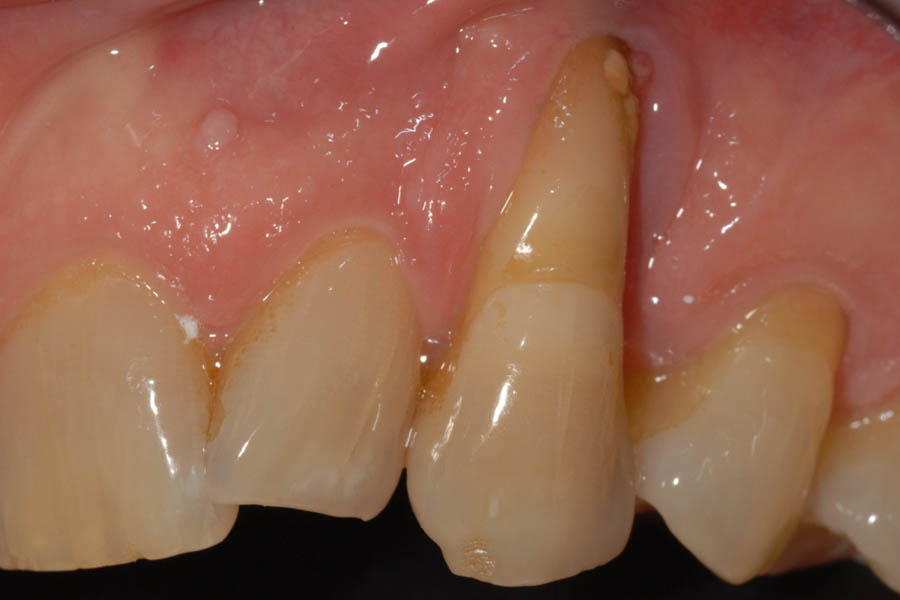

La recessione gengivale è una condizione in cui il margine della gengiva si ritira, esponendo la radice del dente. Questo problema, noto anche come gengive ritirate o gengive retratte, può iniziare in età giovanile e manifestarsi in modo più evidente dopo i 40 anni.

Oltre a compromettere l’estetica del sorriso, causando l’impressione di avere denti più lunghi e dal colore non uniforme, la recessione gengivale può portare a sensibilità dentale e aumentare il rischio di altre patologie. Una delle cause più comuni è uno spazzolamento scorretto e troppo energico, spesso eseguito con spazzolini a setole dure.

- Denti che appaiono più lunghi del normale

- Aumentata sensibilità dentale al caldo e al freddo

Si ricorre alla chirurgia quando la recessione gengivale causa problemi estetici significativi, ipersensibilità, difficoltà di pulizia o precede un trattamento ortodontico. L’obiettivo è ricoprire la radice esposta con un innesto di tessuto. Le moderne tecniche microchirurgiche sono mini-invasive e permettono di trattare più denti in una sola seduta con un disagio post-operatorio minimo.

Ignorare le gengive retratte, specialmente in persone con gengive sottili, può portare a un peggioramento progressivo. La radice esposta non solo causa sensibilità, ma è anche più suscettibile alla carie. L’accumulo di placca diventa più difficile da rimuovere, aumentando il rischio di infiammazione e parodontite, che nei casi più gravi può portare alla perdita del dente (approfondisci perché trattare la recessione gengivale).

Paziente con recessioni gengivali. Trattata con innesti gengivali e faccette dentali.